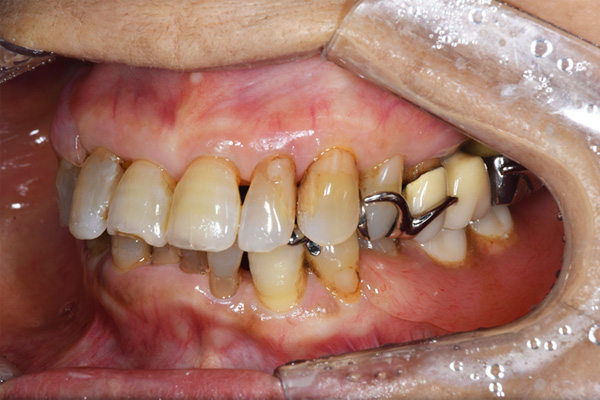

右上のインプラント周囲炎で、その部分が痛いという患者様でした。 また奥歯で噛むことが難しかったため、前歯を使用することが多くなり、 前歯が前よりも前に出てきていることも気になっていらっしゃいました。

インプラント部以外にも歯周病が進行していましたので、歯周病の治療を行いました。 残念ながらインプラントと、1本の歯が残せなかったため抜歯を行いました。 その後、前歯の出っ張りを修正することと入れ歯の安定を図るため、残っている歯を全てかぶせ物にしていくことになりました。 写真中央は抜歯後に入れた治療用の入れ歯になります。 抜歯後歯ぐきが安定しましたら、入れ歯とかぶせ物の型取りを行いました。

噛み合わせチェックでしっかり奥歯で噛めるようにし、 歯を並べます。 その後、それに合わせて前歯を作っていきます。

最終的な入れ歯用の型取りをします。 シリコンで精密に型取りができました。

こちらが完成したかぶせ物と入れ歯です。かぶせ物にはアタッチメントをつけて金属のバネが見えない構造になっています。 入れ歯自体も金属を使用して、極力違和感がでないように、薄く作成しました。

お口の中に入れた状態です。 非常に見た目もよい出来となりました。 バネがみえないと見栄えが全然ちがいます。

治療内容 右上のボーンアンカードブリッジ(インプラントのブリッジ)部分がインプラント周囲炎になり、ぐらぐら揺れてきました。

そのため、インプラントを抜去した後、歯周病の治療と、予後不良の歯を抜歯して、義歯を作成していきました。

見た目が入れ歯とわからない様に針金のない、アタッチメントを使用した入れ歯を作成することにしました。

抜歯後は奥歯でものが噛める様に治療用の入れ歯を作成しました。

また前歯はフレアアウト(奥歯で噛めなくて前歯で噛む様になって、前歯が前に出てくる現象)していたため、患者さんの希望でかぶせ物をすることにしました。